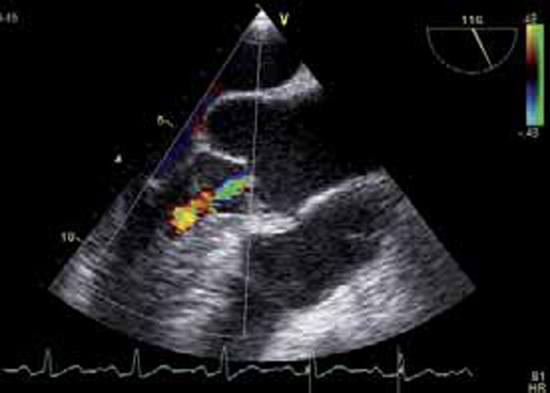

Figure 2 : Zone de convergence du flux régurgitant

En amont de l’orifice aortique, le flux décrit un hémisphère au doppler couleur, c’est la « zone de convergence » ou PISA, dont l’importance permet de quantifier l’IA.